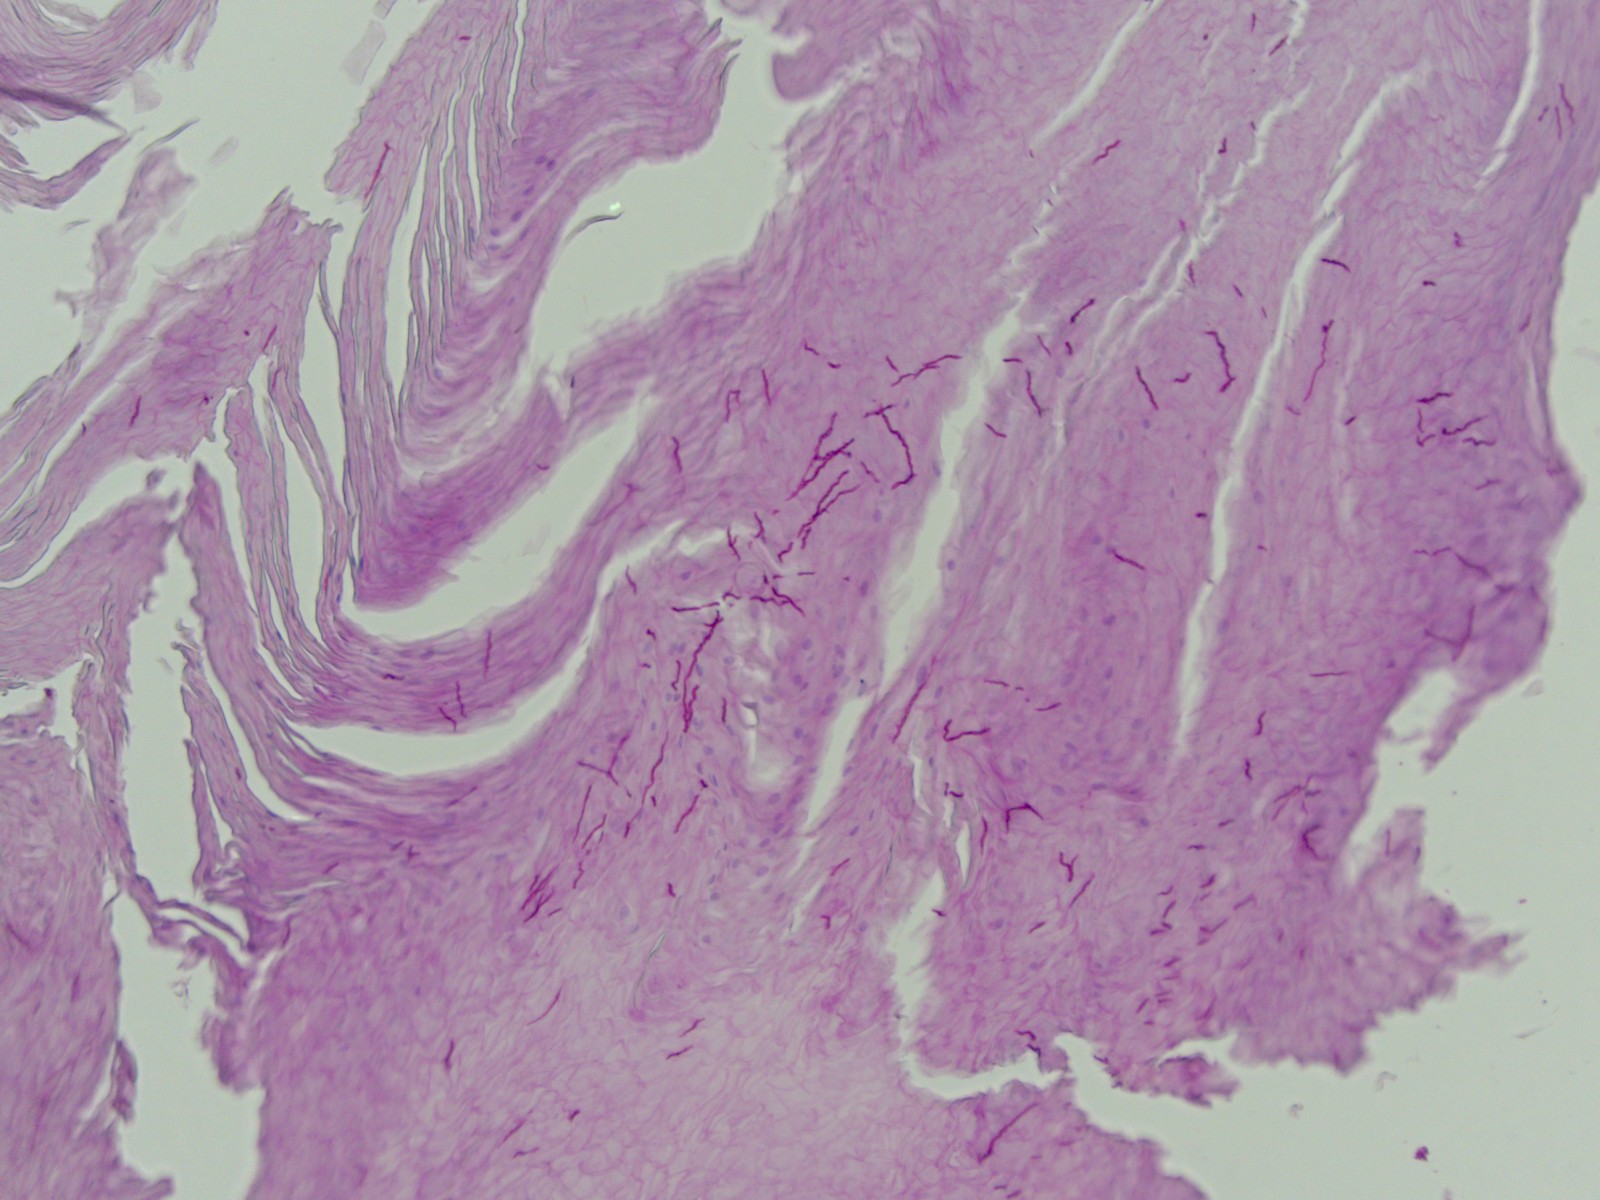

onychomycose (Candida) onychomycose (PA) onychomycose (PA)

PA-Foto's: www.dermpedia.org.

3. Histologie (PAS, sensitiviteit 92%, specificiteit 72%).De hoge sensitiviteit kan nog verder verhoogd worden in combinatie met KOH onderzoek tot 97,8%.